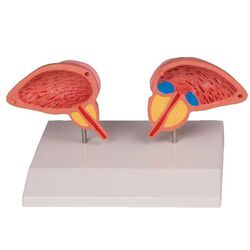

Prostatos modelis, 2 dalių – Erler Zimmer

€97.78 Į krepšelį -